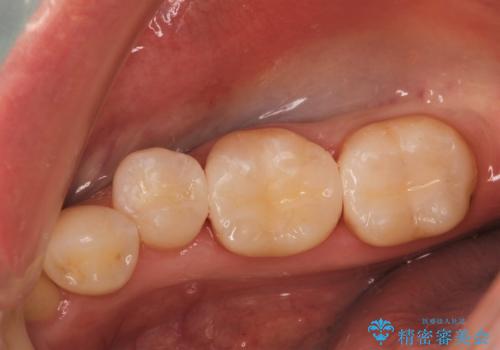

右上2は根管治療が途中のままになっていたようで、前歯3本の根管治療をしてかぶせものを新しくしていく治療計画を立てました。

根管治療は保険で、それ以外は自費治療で行いました。